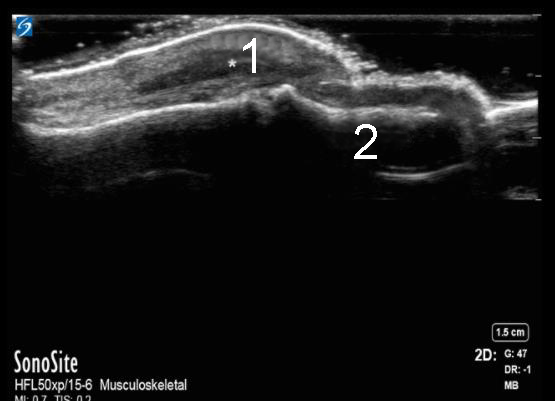

Hand Tendon Inflammation Image

Inflammation

Distal Phalanx